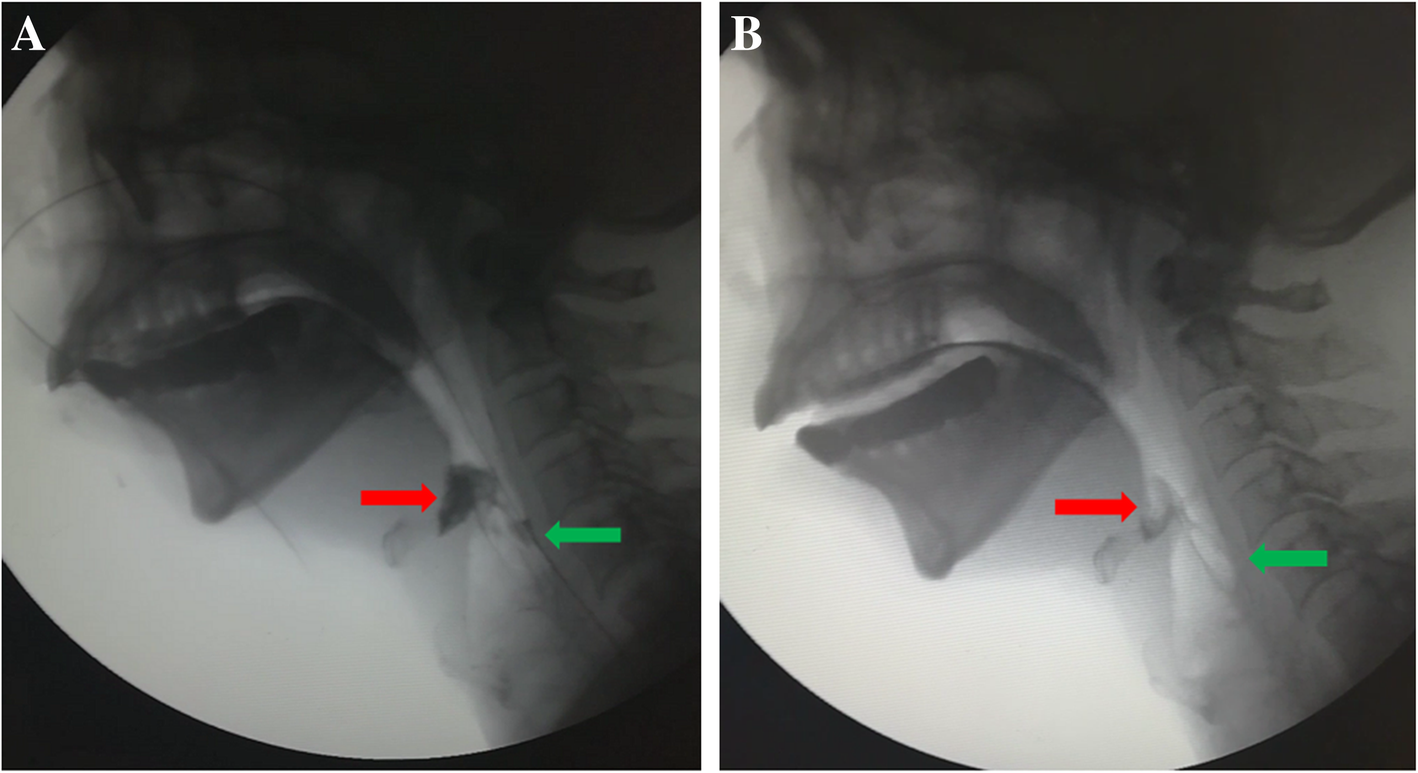

From www.researchgate.net

(PDF) Balloon Dilatation for an Esophageal Stricture by LongTerm Use of a Nasogastric Tube A Ng Tube Long Term Effects If you end up needing enteral. this is why it is important to confirm the placement each time before a feed. Nasogastric and nasoenteric tubes are flexible double or single lumen tubes that are passed. It’s only designed to be used for up to six weeks. how long can an ng tube stay in? using an ng. Ng Tube Long Term Effects.